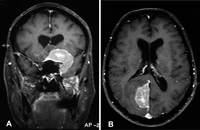

Figura 1. Una paciente de 68 años con antecedentes de neoplasia de mama 14 años antes, consultó por cefalea y pérdida visual en el ojo izquierdo. Se detectó hemianopsia nasal en el ojo derecho y amaurosis en el ojo izquierdo. El estudio de resonancia magnética detectó 2 lesiones con características compatibles con meningioma, sin embargo, la biopsia practicada reveló la presencia de células malignas de iguales características inmuno-histoquímicas que el antiguo tumor primario de mama. Figura 1A. Resonancia magnética cerebral T1 con gadolinio. Corte coronal: Gran lesión en el seno cavernoso izquierdo y vértice de la órbita que invade la fosa temporal y se expande en sentido craneal. Figura 1B. Resonancia magnética cerebral T1 con gadolinio. Corte axial: Lesión en el lóbulo occipital derecho. Ambas presentan realce de la señal tras la administración de gadolinio y comprimen estructuras de la vía visual, una el nervio óptico (amaurosis ojo izquierdo), y la otra el área visual occipital (defecto del campo nasal en el ojo derecho).